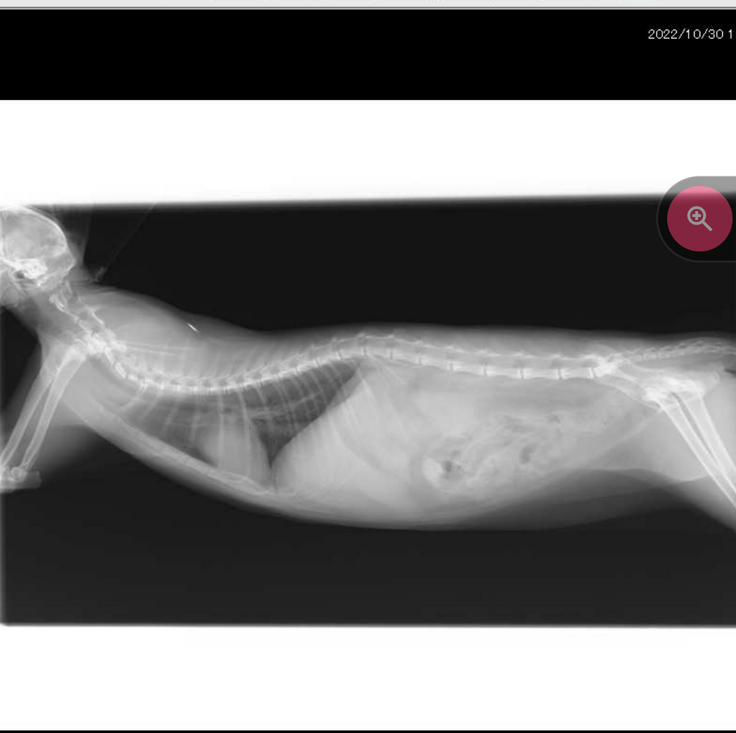

FIPという結論は以下の血液検査やエコー検査により腎臓や目などに多くの肉芽腫がみられ、やや腹水が見受けられることから、ドライタイプ中期と診断されました。

【病院から掲載の許諾を得ております】